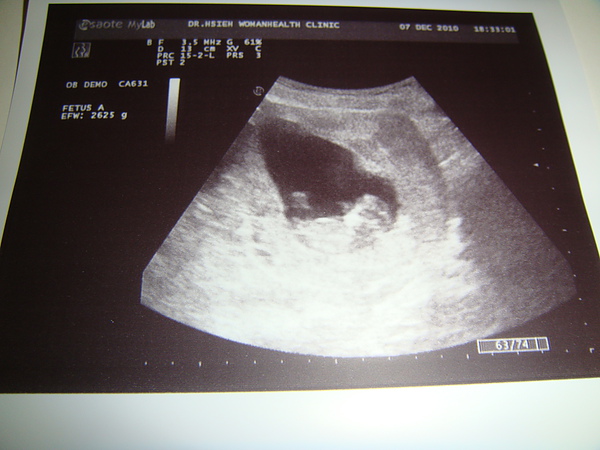

第二胎在我們計畫中的時間到來

預產期是在明年六月

我跟老公很開心的歡迎他 未來加入我們的生活